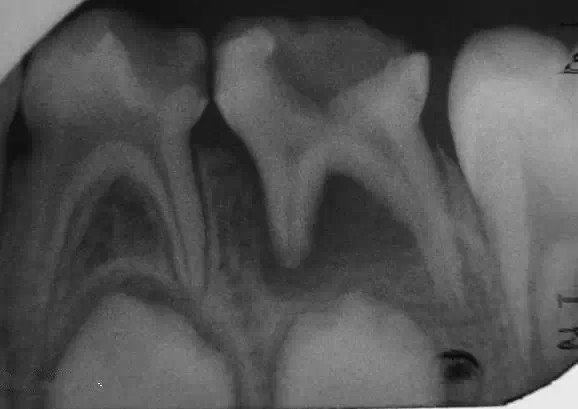

1.jpg

乳牙根尖周病是指根尖周圍或根分叉部位的牙骨質(zhì)、牙周膜和牙槽骨等組織的炎癥性疾病,其病因和臨床表現(xiàn)均有其特點。(引自醫(yī)科大 課件)

乳牙牙髓壞死的診斷很重要!

A,如果小孩子以前的牙痛癥狀不是很明顯或是說不清楚,在檢查時又不會痛,就有可能忽略了乳牙牙髓的診斷。

B,乳牙慢性根尖炎癥,往往可有潛在的細(xì)小的瘺孔或是已經(jīng)處于半閉合狀態(tài)的瘺管,而周圍并無明顯的炎癥的,存在局部牙齦淤血的,很容易被忽略。

C,如果按照一般深齲洞而直接充填的,填補以后非常容易發(fā)生急性根尖周炎癥,形成齒槽膿腫。

D,在臨床上,有時看到的齲洞不深,又沒有穿髓孔,但細(xì)菌及其毒力可能已經(jīng)進(jìn)入牙髓,造成(導(dǎo)致)牙髓的壞死。

2.jpg

3.jpg

乳牙急性根尖周炎的應(yīng)急處理,首先應(yīng)建立髓腔引流,用快速鋒利的渦輪機(jī)牙鉆開髓,開放髓腔,使炎性滲出物或膿液通過根管引流。 (福建醫(yī)大口腔醫(yī)院 高生輝老師的圖片)